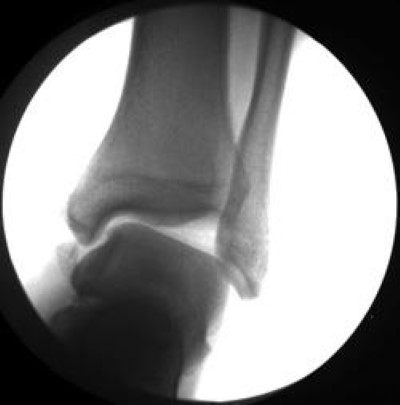

3 major lateral ankle ligaments: The lateral ligaments of the ankle joint are among the ligaments most often injured. The anterior talofibular ligament (atfl), which connects the front of the talus bone to a long bone in the lower leg called the fibula the calcaneofibular ligament (cfl), which connects the calcaneus, or heel bone, to the fibula Important ligaments of the ankle are those that compose the distal tibiofibular syndesmosis and the lateral and medial collateral ligaments (, 1,, 2). Ligaments stabilizing the ankle joint.

Injuries typically occur during plantar flexion and inversion; The anterior talofibular ligament attaches the anterior margin of the lateral malleolus to the adjacent region of the talus bone. Within the 3 ligaments of the lateral ligament complex, 80% of patients tear the anterior talofibular ligament (atfl), whereas the other 20% of patients tear the atfl and calcaneofibular ligament (cfl). The lateral ankle ligament complex consists of three ligaments: What are the 3 ligaments that make up the lateral ligament complex of the ankle? Anterior talofibular (atf) (most commonly sprained), calcaneofibular (cf), and posterior talofibular (ptf); Chronic ankle instability following ankle sprains causes pain and functional problems such as recurrent giving way. 1) the anterior talofibular ligament.

Three ligaments on the outside of the ankle that make up the lateral ligament complex, as follows: The medial (deltoid) ligaments is much stronger than the lateral ligament and is therefore injured much less frequently. Within the 3 ligaments of the lateral ligament complex, 80% of patients tear the anterior talofibular ligament (atfl), whereas the other 20% of patients tear the atfl and calcaneofibular ligament (cfl). Ligaments stabilizing the ankle joint. 1) the anterior talofibular ligament. Without thorough and complete rehabilitation, the ligament or surrounding muscles may remain weak, resulting in recurrent instability. The three ligaments are together called the lateral collateral ligament complex. Together they constitute the lateral ligament complex. If there is a complete tear of the ligaments, the ankle may become unstable after the initial injury phase passes. We dissected cadaveric ankles free of skin and soft tis sue and. The most frequently injured lateral ankle ligament is the anterior tfl (66% of cases), followed by a combination of this ligament and the cfl (20%) (, 5). Chronic ankle instability following ankle sprains causes pain and functional problems such as recurrent giving way. The lateral collateral ligament (complex) of the ankle is a set of three ligaments that resist inversion of the ankle joint.they are more commonly injured than the medial collateral (deltoid) ligament of the ankle.they run from the lateral malleolus of the fibula to the talus and calcaneus.

Within the 3 ligaments of the lateral ligament complex, 80% of patients tear the anterior talofibular ligament (atfl), whereas the other 20% of patients tear the atfl and calcaneofibular ligament (cfl). The anterior talofibular ligament attaches the anterior margin of the lateral malleolus to the adjacent region of the talus bone. Chronic ankle instability following ankle sprains causes pain and functional problems such as recurrent giving way. The most common cause for a persistently painful ankle is incomplete healing after an ankle sprain. We believe a knowledge of this precise anatomy is im portant to better reconstruct or repair lateral ligaments. The anterior tibiofibular (atfl), calcaneofibular (cfl) and posterior talofibular (ptfl) ligaments. When you sprain your ankle, the connecting tissue between the bones is stretched or torn. The medial (deltoid) ligaments is much stronger than the lateral ligament and is therefore injured much less frequently. The three ligaments are together called the lateral collateral ligament complex. The atfl resists torsion and inversion stresses in a. Important ligaments of the ankle are those that compose the distal tibiofibular syndesmosis and the lateral and medial collateral ligaments (, 1,, 2). Which is most commonly sprained? 1) the anterior talofibular ligament.